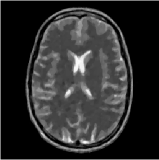

In this experiment, we use Shepp-Logan and the Brain phantom with resolution () and () respectively as the benchmark dataset. The simulated flat detector X-ray system is configured with , mm, mm and , mm, mm. The detectors are spaced by mm with bin width mm and the projectors are uniformly spaced over . Fig. 12 shows the reconstruction result of Shepp-Logan phantom. The (imperfect) reconstruction achieved by reference projector in Fig. 12(a) illustrates the practical reconstruction problem from limited-view projection. The approximating projector made by LTRI results in a less accurate reconstruction (the resolution of look-up table in LTRI is ). SF makes a slightly more accurate approximation and achieves a little higher quality over LTRI. Our method provides a reconstruction that can achieve the same quality as the one provided by reference projector.

Fig. 13 shows the reconstruction of the brain phantom. In order to evaluate the impact of the accuracy of the forward model in image reconstruction, we visualize the differences of all reconstructions from the reconstruction provided by reference model that is shown in 13(a). For visualization purpose, we scale the errors by appropriate factors shown in captions. The SNRs for these results are (Ref) dB, (LTRI) dB, (SF) dB, (CNSF) dB respectively.

This experiment shows significant improvements over LTRI and SF methods in image reconstruction.